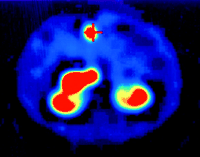

Radiopeptides emitting β-radiation have superior therapeutic potential since the particles they emit have sufficient energy to cause cell damage without penetrating very far into surrounding tissue (Wiseman & Kvols 1995). A high-energy β-emitter attached to a SST analogue could potentially deliver a lethal dose of radiation to a SST-positive tumour with minimal damage to healthy tissue (Wiseman & Kvols 1995, de Jong et al. 2003). Despite its diagnostic use, DTPA-octreotide is not suitable for labelling with yttrium-90 (90Y), a pure energetic β-emitter well suited for internal radiotherapy; this has led to the development of a new peptide chelator that can be stably labelled with 111In and 90Y (de Jong et al. 1997, Krenning et al. 1999a). The same SST analogue (Tyr3-octreotide) used for diagnosis has been coupled to the bifunctional chelating agent (1,4,7,10-tetraazacyclododecane-N,N′,N″,N‴-tetraacetic acid, DOTA0) for the complexing of 90Y (de Jong et al. 1997, Krenning et al. 1999a) (Fig. 2⇑). In contrast to 90Y-DTPA-octreotide, 90Y-DOTA-D-Phe1-Tyr3-octreotide (90Y-SMT487, OctreoTher, 90Y-DOTATOC) shows no dissociation from the DOTA-chelated peptide in serum and can deliver tumouricidal doses of radiation by targeting SST-positive tumours that have demonstrated uptake on a diagnostic 111In-pentetreotide scan (OctreoScan) (de Jong et al. 1997). Furthermore, while, in general, 90Y-DOTA-D-Phe1-Tyr3-octreotide is a non-γ-emitter, the β-particles can cause localized release of γ-activity from affected cells (Bremsstrahlung), making some imaging of the effectiveness of therapy possible (Kaltsas et al. 2004a) (Fig. 3⇓).

Reconstructed SPECT image of a malignant insulinoma imaged with 90Y-octreotide at 24 h. Note that the primary tumour is clearly shown (Indicated by the cross). The radiation from this predominantly β-emitter is secondary radiation, Bremsstrahlung.